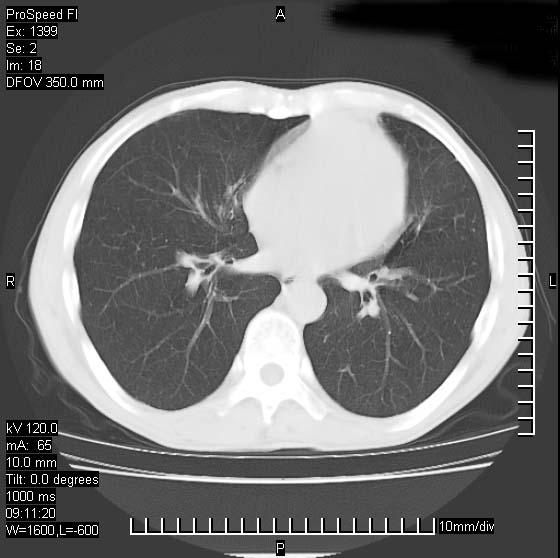

以下是引用卜一在2007-1-19 9:55:00的发言:[br]左肺沿胸膜下巨大肿块影,边缘呈分叶征,纵隔内见肿大淋巴结,右肺内另见一不规则结节影 .考虑:左肺周围性肺癌伴纵隔 右肺内转移.

以下是引用rgsyyf在2007-1-19 11:05:00的发言:[br]左肺上叶见形态不规则巨大软组织肿块影,边缘呈分叶征,纵隔内隆突下见肿大淋巴结,右肺内另见一不规则结节影 .考虑:左肺周围性肺癌伴纵隔即右肺内转移.